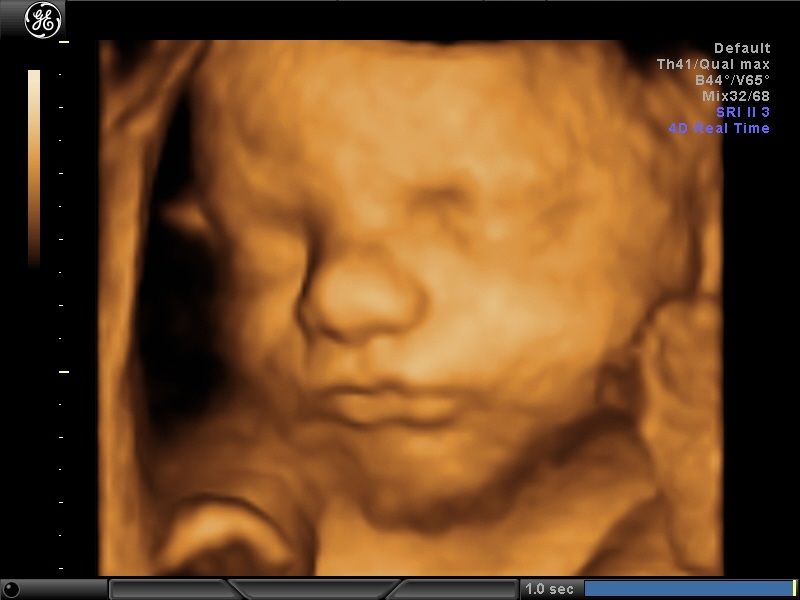

Wykonuję tam około 600 badań „I trymestru ciąży” rocznie, co daje łącznie około 1200 badań z „II trymestrem ciąży” włącznie. Od 15 lat w swoim gabinecie również wykonuję badania prenatalne I, II i III trymestru ciąży w znacznej ilości. To umożliwia mi osiągnięcie doskonałych wyników w diagnostyce tych badań, co stawia mnie w czołówce specjalistów diagnostyki prenatalnej.

Większość swojej kariery zawodowej spędziłem na sali porodowej oraz patologii ciąży. Aktualnie pracuję na sali porodowej. Mam 15-letnie doświadczenie w diagnostyce prenatalnej poparte dużą ilością przebadanych pacjentek i posiadam najszerszy wachlarz certyfikatów z zakresu ultrasonografii płodowej. Corocznie uczestniczę w szkoleniach i kursach ultrasonograficznych.

- diagnostyka prenatalna I,II i III trymestru ciąży z przepływami dopplerowskimi, testem podwójnym (PAPPA i B-HCG), oznaczanie DNA płodowego NIPTY, testy SANCO, NIFTY, VERACITY